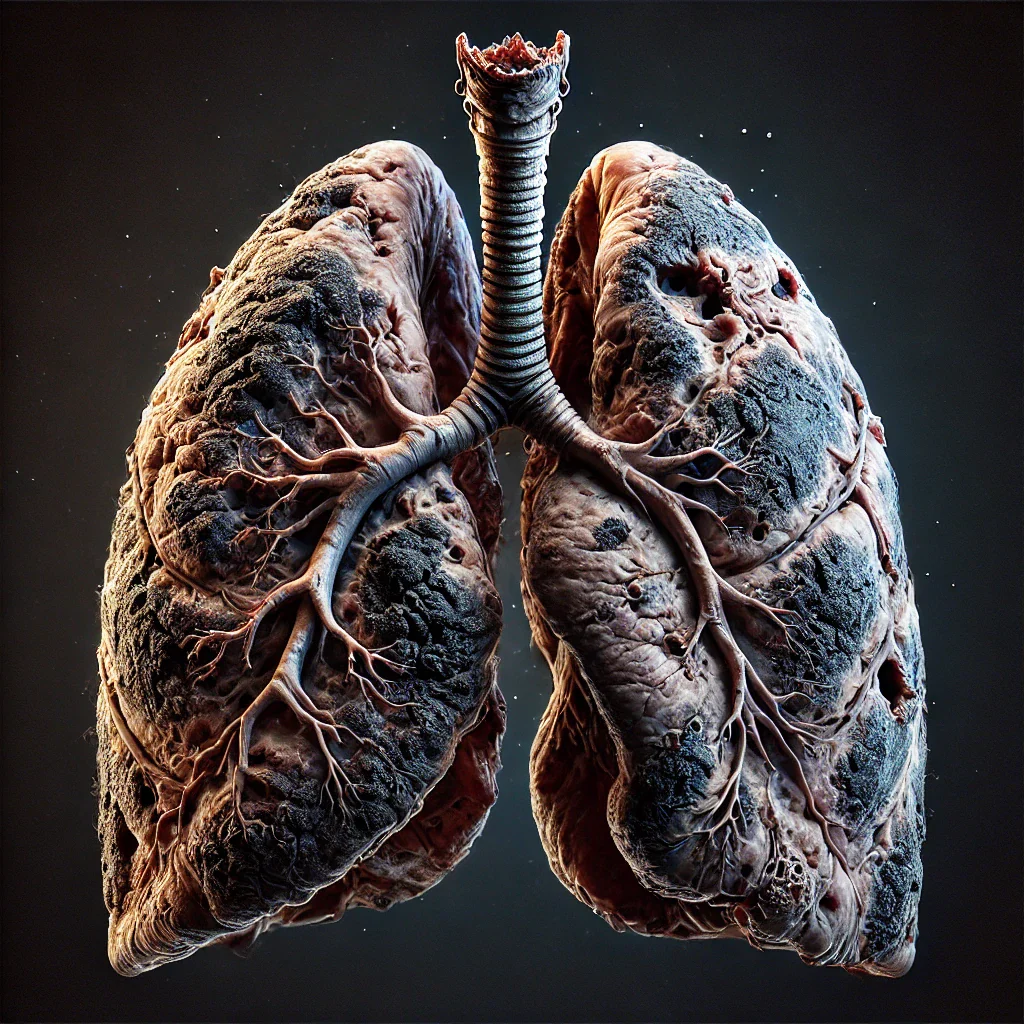

Your Lungs Need You

Interact with the image below for a fun, exaggerated representation of what quitting addictions and training your lungs can do!

Smoking & Vaping

Years of smoking or vaping can weaken lung function, reduce oxygen intake, and create a dependence on hand-to-mouth habits. The Inex-Air helps break the cycle by replacing unhealthy habits with a purposeful, structured breathing tool that strengthens your lungs while keeping your hands engaged.

-Lung Recovery – Train your lungs to regain strength, improve capacity, and breathe easier.

-Reduce Breathlessness – Improve airflow and endurance for easier, deeper breathing.